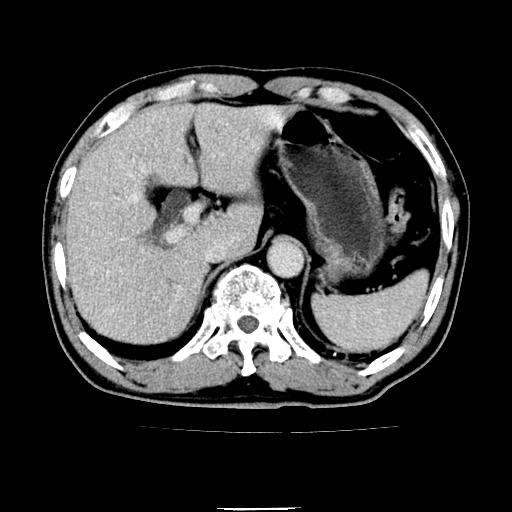

以下是引用chenqiong在2010-3-25 20:56:00的发言:[br]1、胆囊炎,胆囊息肉[br]2、肝内胆管及胆总管扩张,胆总管下端结石[br]3、十二指肠乳头旁憩室

以下是引用zxl51642在2010-3-26 10:47:00的发言:[br]胆囊炎,胆囊息肉,胆总管扩张,但未看到明显肿块,肝内胆管扩张不像恶性,炎性狭窄或阴性结石可能吧,建议mrcp,右肾小囊肿